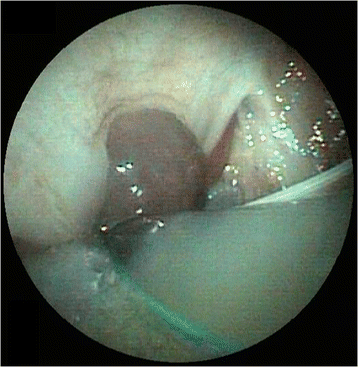

Five hours after extubation, the dog developed stridor and evidence of upper airway obstruction that worsened rapidly. The dog was agitated, tachypneic and cyanotic on room air and was immediately transferred to the operating room to secure the airway. Intubation was attempted via direct visualization with laryngoscopy, but this was difficult because of the size of the hematoma. The epiglottis was not visualized and the correct position of the endotracheal tube was confirmed using capnography. On examination of the oral cavity and oropharynx, there was an ecchymotic swelling of the soft palate. Laryngoscopy confirmed extensive hematoma; pharyngoscopy demonstrated a soft, bulging, violaceous mass involving the lateral and dorsal pharyngeal walls (Fig. 1). A lateral cervical radiograph revealed marked prevertebral soft tissue swelling (Fig. 2). The dog was then transferred to the magnetic resonance imaging (MRI) unit under general anesthesia, and urgent MRIFootnote 3 of the neck was performed (Fig. 3). MRI revealed a retropharyngeal mass with features consistent with hemorrhage; the trachea was outlined only by the endotracheal tube and the mass was causing dorsal compression of the airway.

In this case, a flexible laryngoscope confirmed the diagnosis. The role of flexible pharyngoscopy cannot be overemphasized. Even a small bulging of the posterior wall of the pharynx should alert clinicians and guide the clinical strategy towards a high suspicion of a retropharyngeal space-occupying lesion [18]. Computed tomography is also important to confirm the diagnosis and to assess the extent of the hematoma and its relation to structures in the neck [6]. MRI offers several advantages over computed tomography regarding multiplanar anatomic display and superior soft tissue contrast, allowing more specific diagnoses to be made [19]. MRI not only better depicts the extent of retropharyngeal lesions but, most importantly, is able to identify acute and subacute blood products, thereby affecting both diagnosis and management. MRI is sensitive to blood products in different stages of evolution because of their paramagnetic signal properties, which change over time depending on the dominant component (e.g., acute deoxyhemoglobin, subacute intra- or extracellular methemoglobin, and chronic hemicromes).